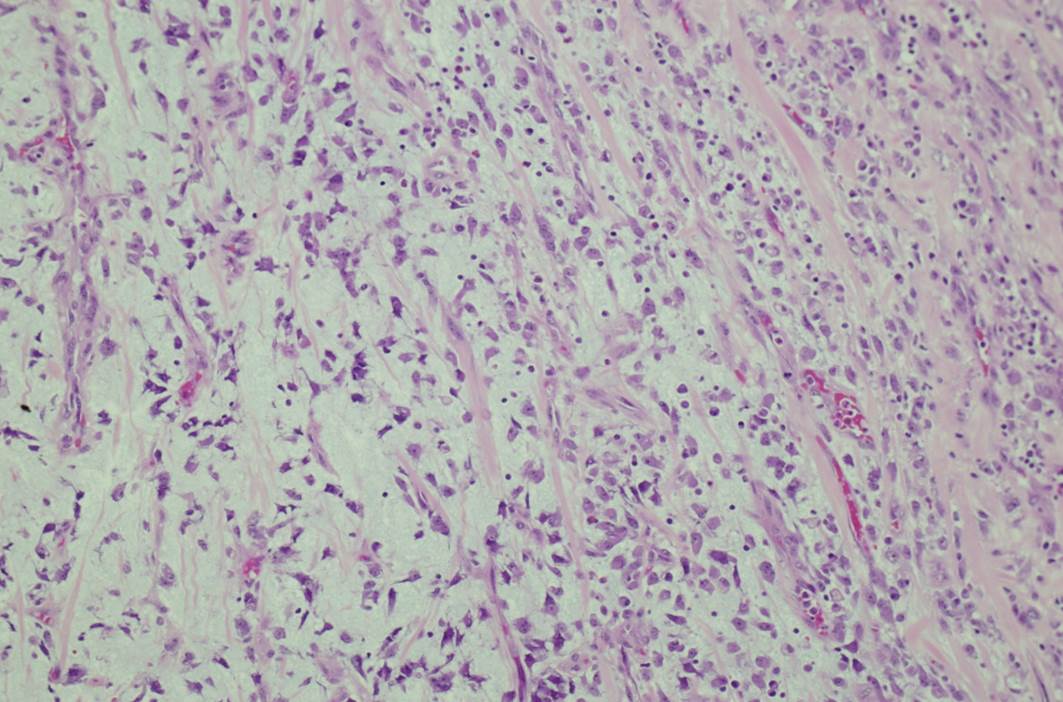

Микрофотографии гистологии глиобластомы головного мозга